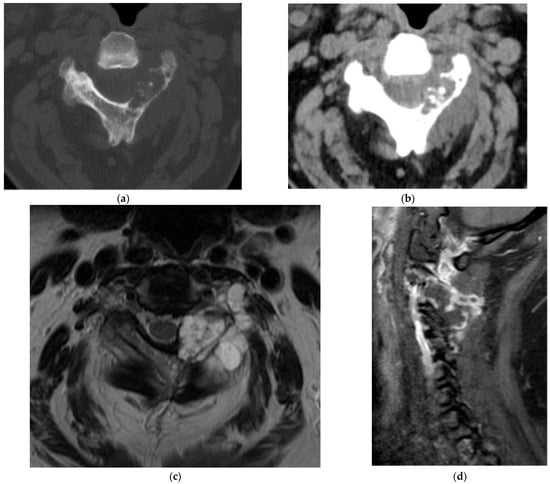

2.3.2. Chordoma